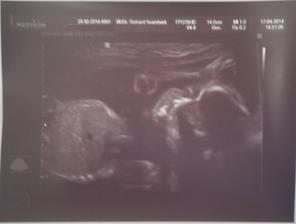

Jáchymek - -9. až 0. měsíc 🙂 - 2. těhotenství

24. srpna 2014 - 39+2tt - ve 4:24 hod. s mírami 49 cm a 2,97 kg se nám po náročném (pupečník kolem krku), ale zato rychlém porodu narodil náš druhý poklad. Šimonek mu vybral jméno Jáchym, my s tatínkem doplnili druhé jméno Pavel - JÁCHYM PAVEL KOLAŘÍK.